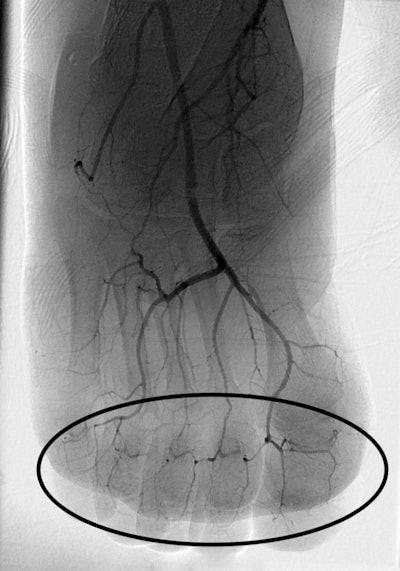

Lee and Higgins sought to evaluate the efficacy of intra-arterial and intravenous tPA therapies to treat these injuries and reduce the need for amputation. They reviewed 157 studies, finally including 16 that described using intra-arterial and intravenous tPA. The studies consisted of 209 patients with 1,109 digits at risk of amputation. In 15 of the 16 studies, patients were initially evaluated using digital subtraction angiography (DSA) or triple-phase bone scans.

- Use DSA to assess areas of impaired perfusion. DSA can also be used to start intra-arterial infusion therapy.